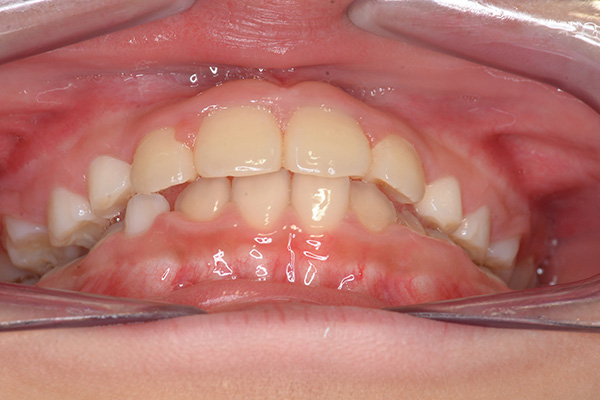

動的治療開始前(9歳7ヵ月)

動的治療開始前

(9歳7ヵ月)

IOP

口腔内所見 over jet -2.5mm、over bite 2.0mm、大臼歯関係はⅠ級 。Hellmanのdental ageはⅡCであり前歯部は反対咬合を呈していた。